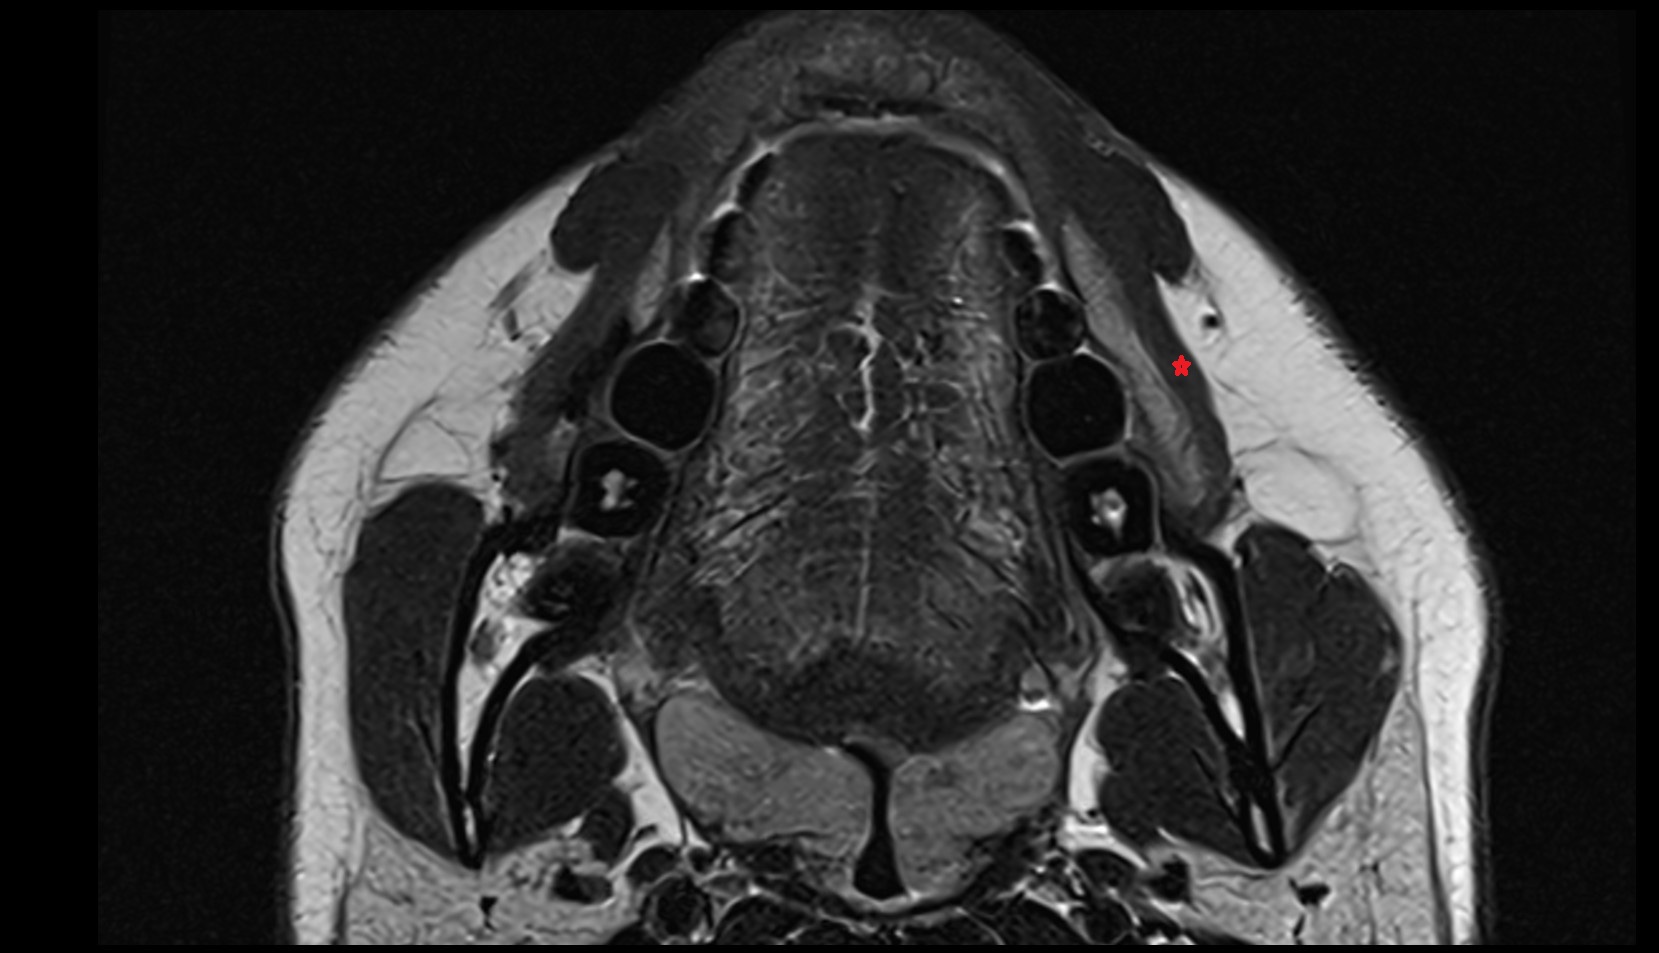

- Temporomandibular joint

- Mandibular condyle

- Articular disc of temporomandibular joint

- Articular eminence

- Lateral pterygoid muscle

- Masseter muscle

- Temporalis muscle